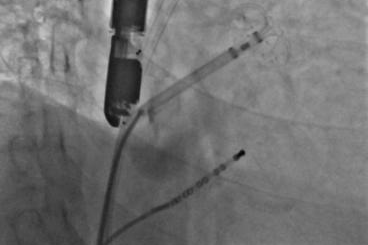

▲实现后取出脑;ぷ爸,均未见血栓

其中首场公开演示的左心耳血栓封堵病例拥有极高难度,患者术前TEE显示左心耳血栓形成伴机化,血栓位于心耳中段,近中端絮状物显著。封堵机遇只有一次,选型和操作稍有失误,城市增长手术风险。因而手术采取全麻,并装置了抗栓塞脑动脉;ぷ爸,以削减术中风险。通过TEE疏导下丈量左心耳大幼以及确认左心耳血栓地位,李岳春教授凭借自身丰硕经验最终决定使用LAmbre 2632型号,选取推送式植入法将左心耳血栓牢牢锁死于远端,并且封堵器一次成型,封堵成效极佳,实现后取出脑;ぷ爸,均未见血栓,顺利实现了此台高难度的手术,获得了学员们的一致认可。